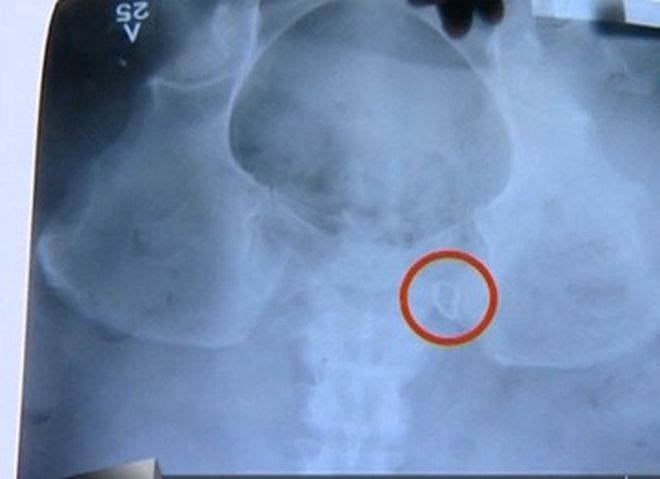

Личният лекар на Траяна я посъветвал да отиде на скенер, за да разберат какво ѝ причинява непоносимите болки. Апаратът показал, че в тялото ѝ има забравена макара. Въпреки уверенията на хирурзите, че това е невъзможно и всичко с повторната операция е наред, болките на Траяна ставали все по-нетърпими.

Жертвата на двойната лекарска грешка потърсила второ мнение в друга болница и след много ехографии и рентгенови снимки лъсна истината, че в тялото ѝ има чуждо тяло с размер 35-40 мм.